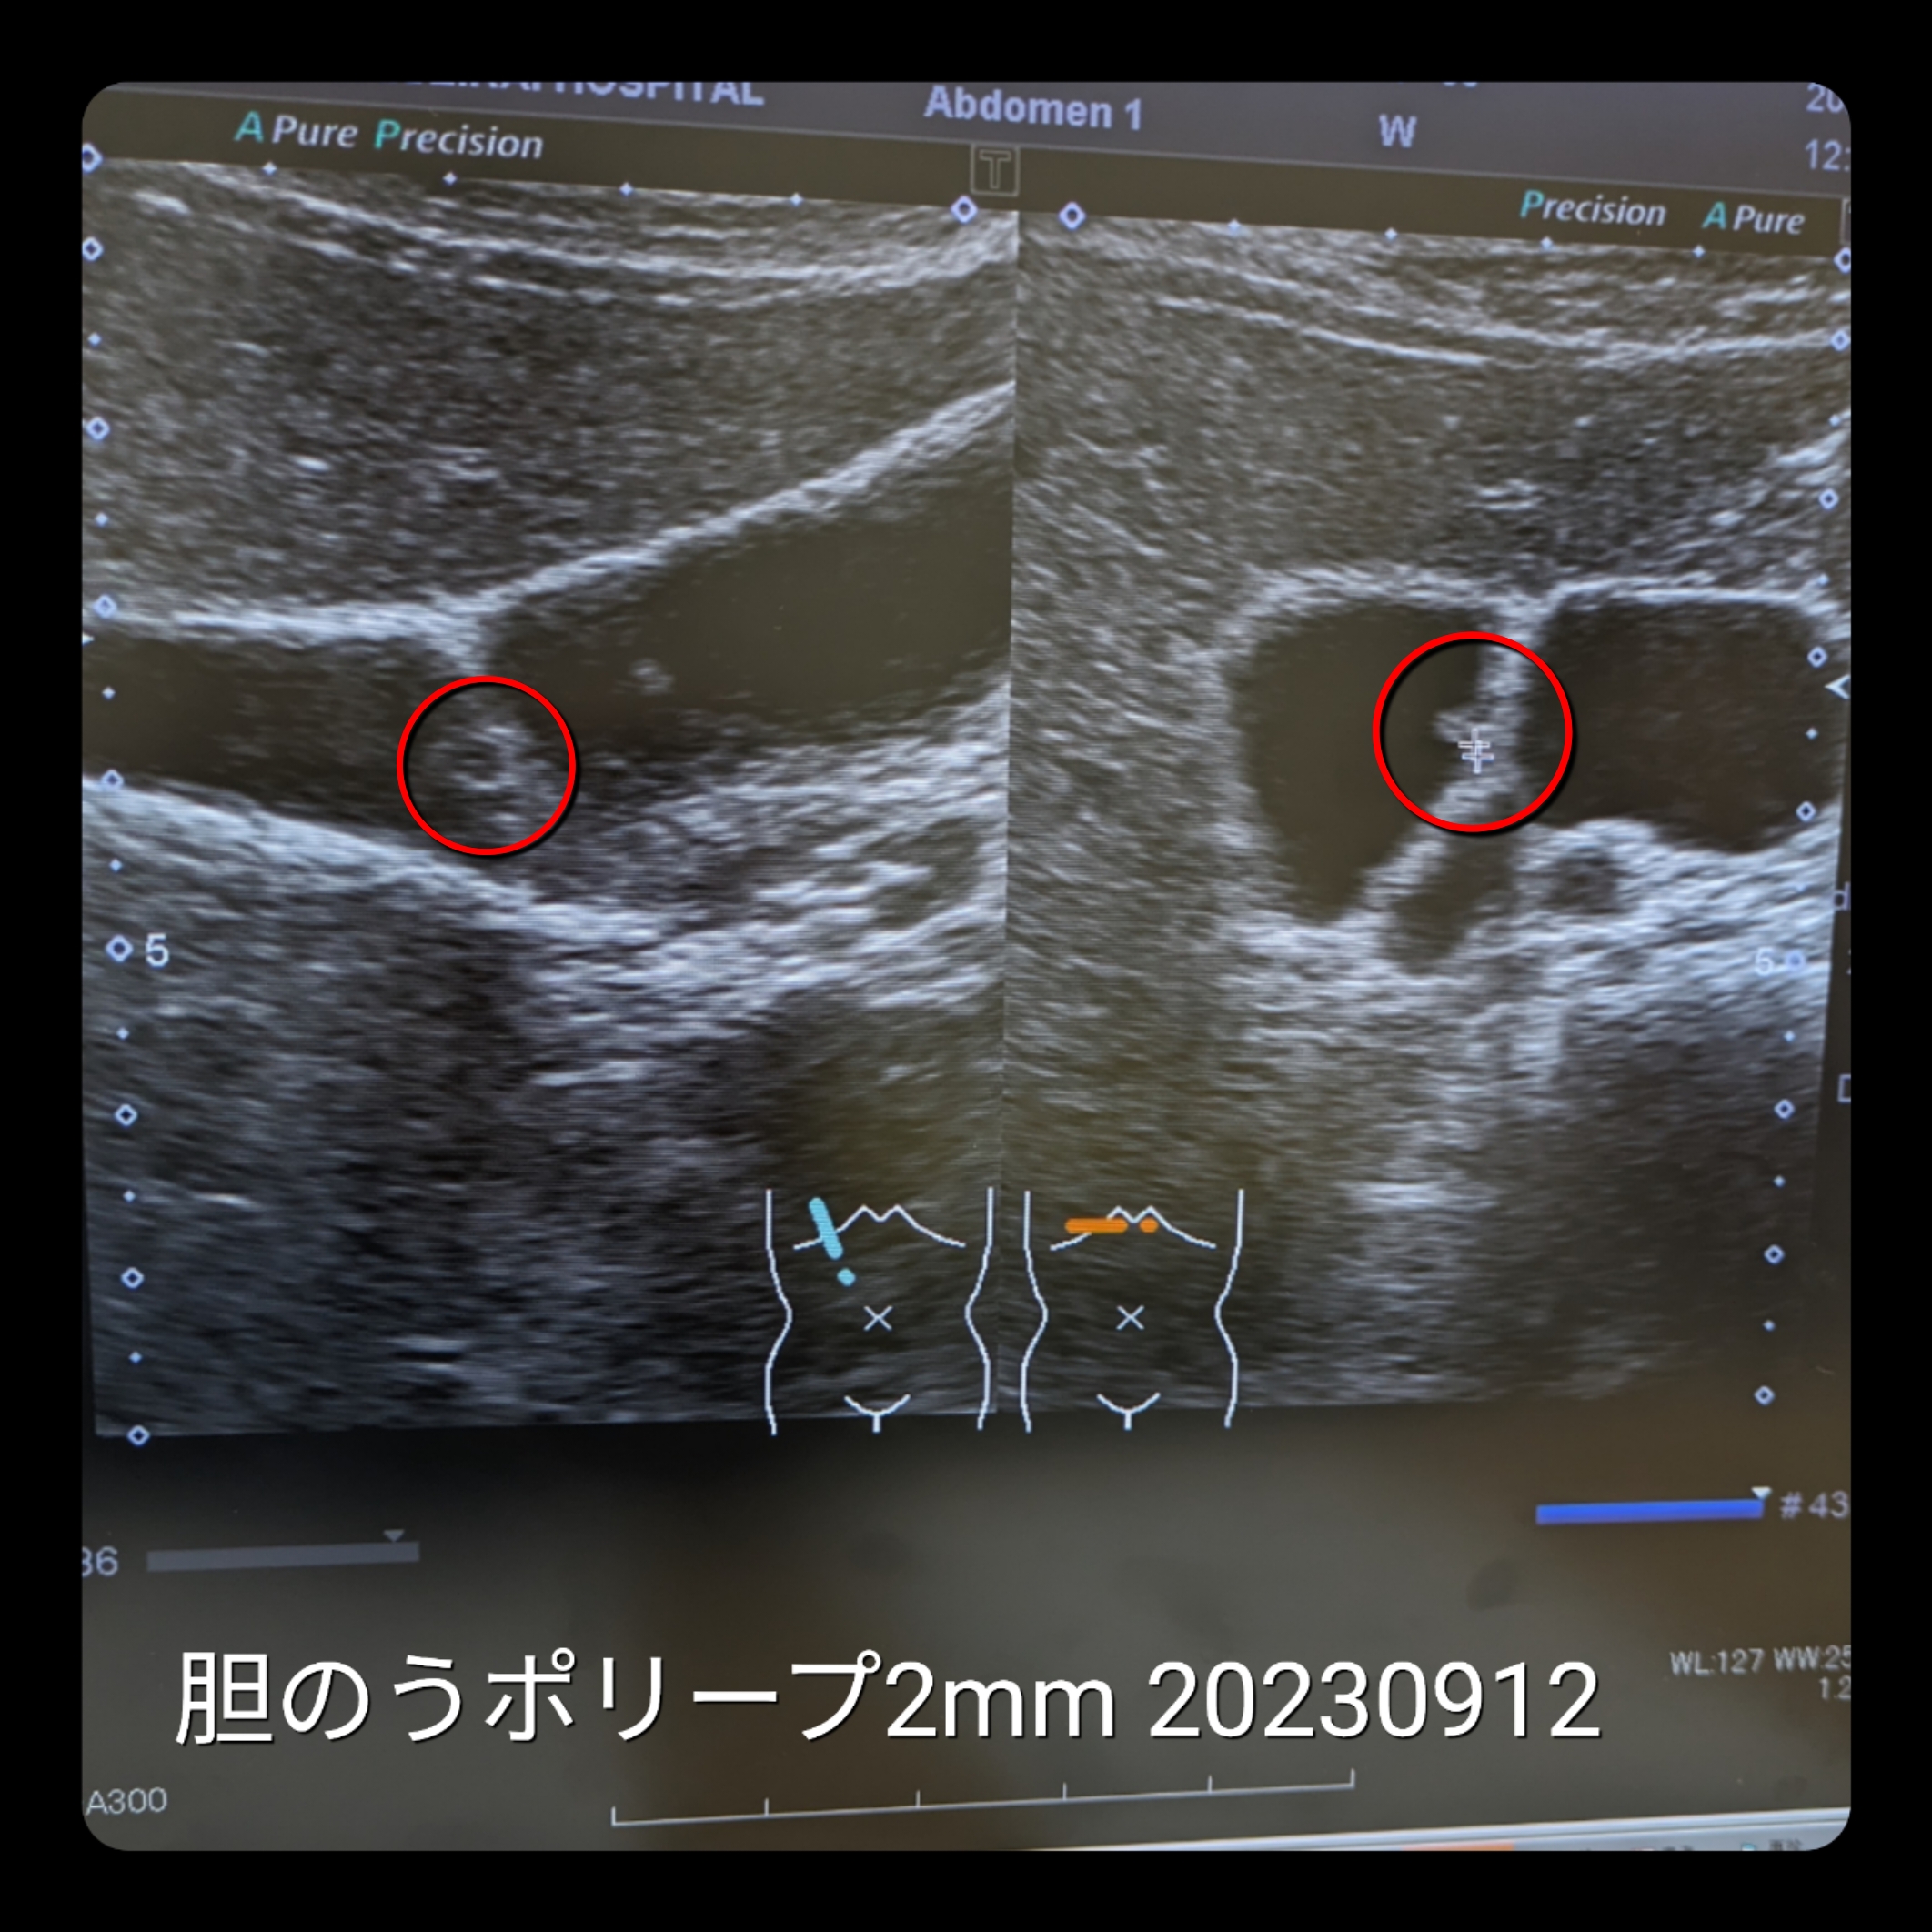

2023.09.12

新たに

胆のうポリープが発見された

2mmで大したことない

1cmより大きくなるようだったら

切除になるが

今は気にすることはない